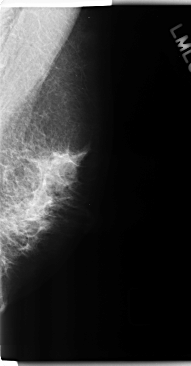

C_0198_1.LEFT_MLO

LEFT_MLO LINES 4752 PIXELS_PER_LINE 2480 BITS_PER_PIXEL 12 RESOLUTION 50 NON_OVERLAY